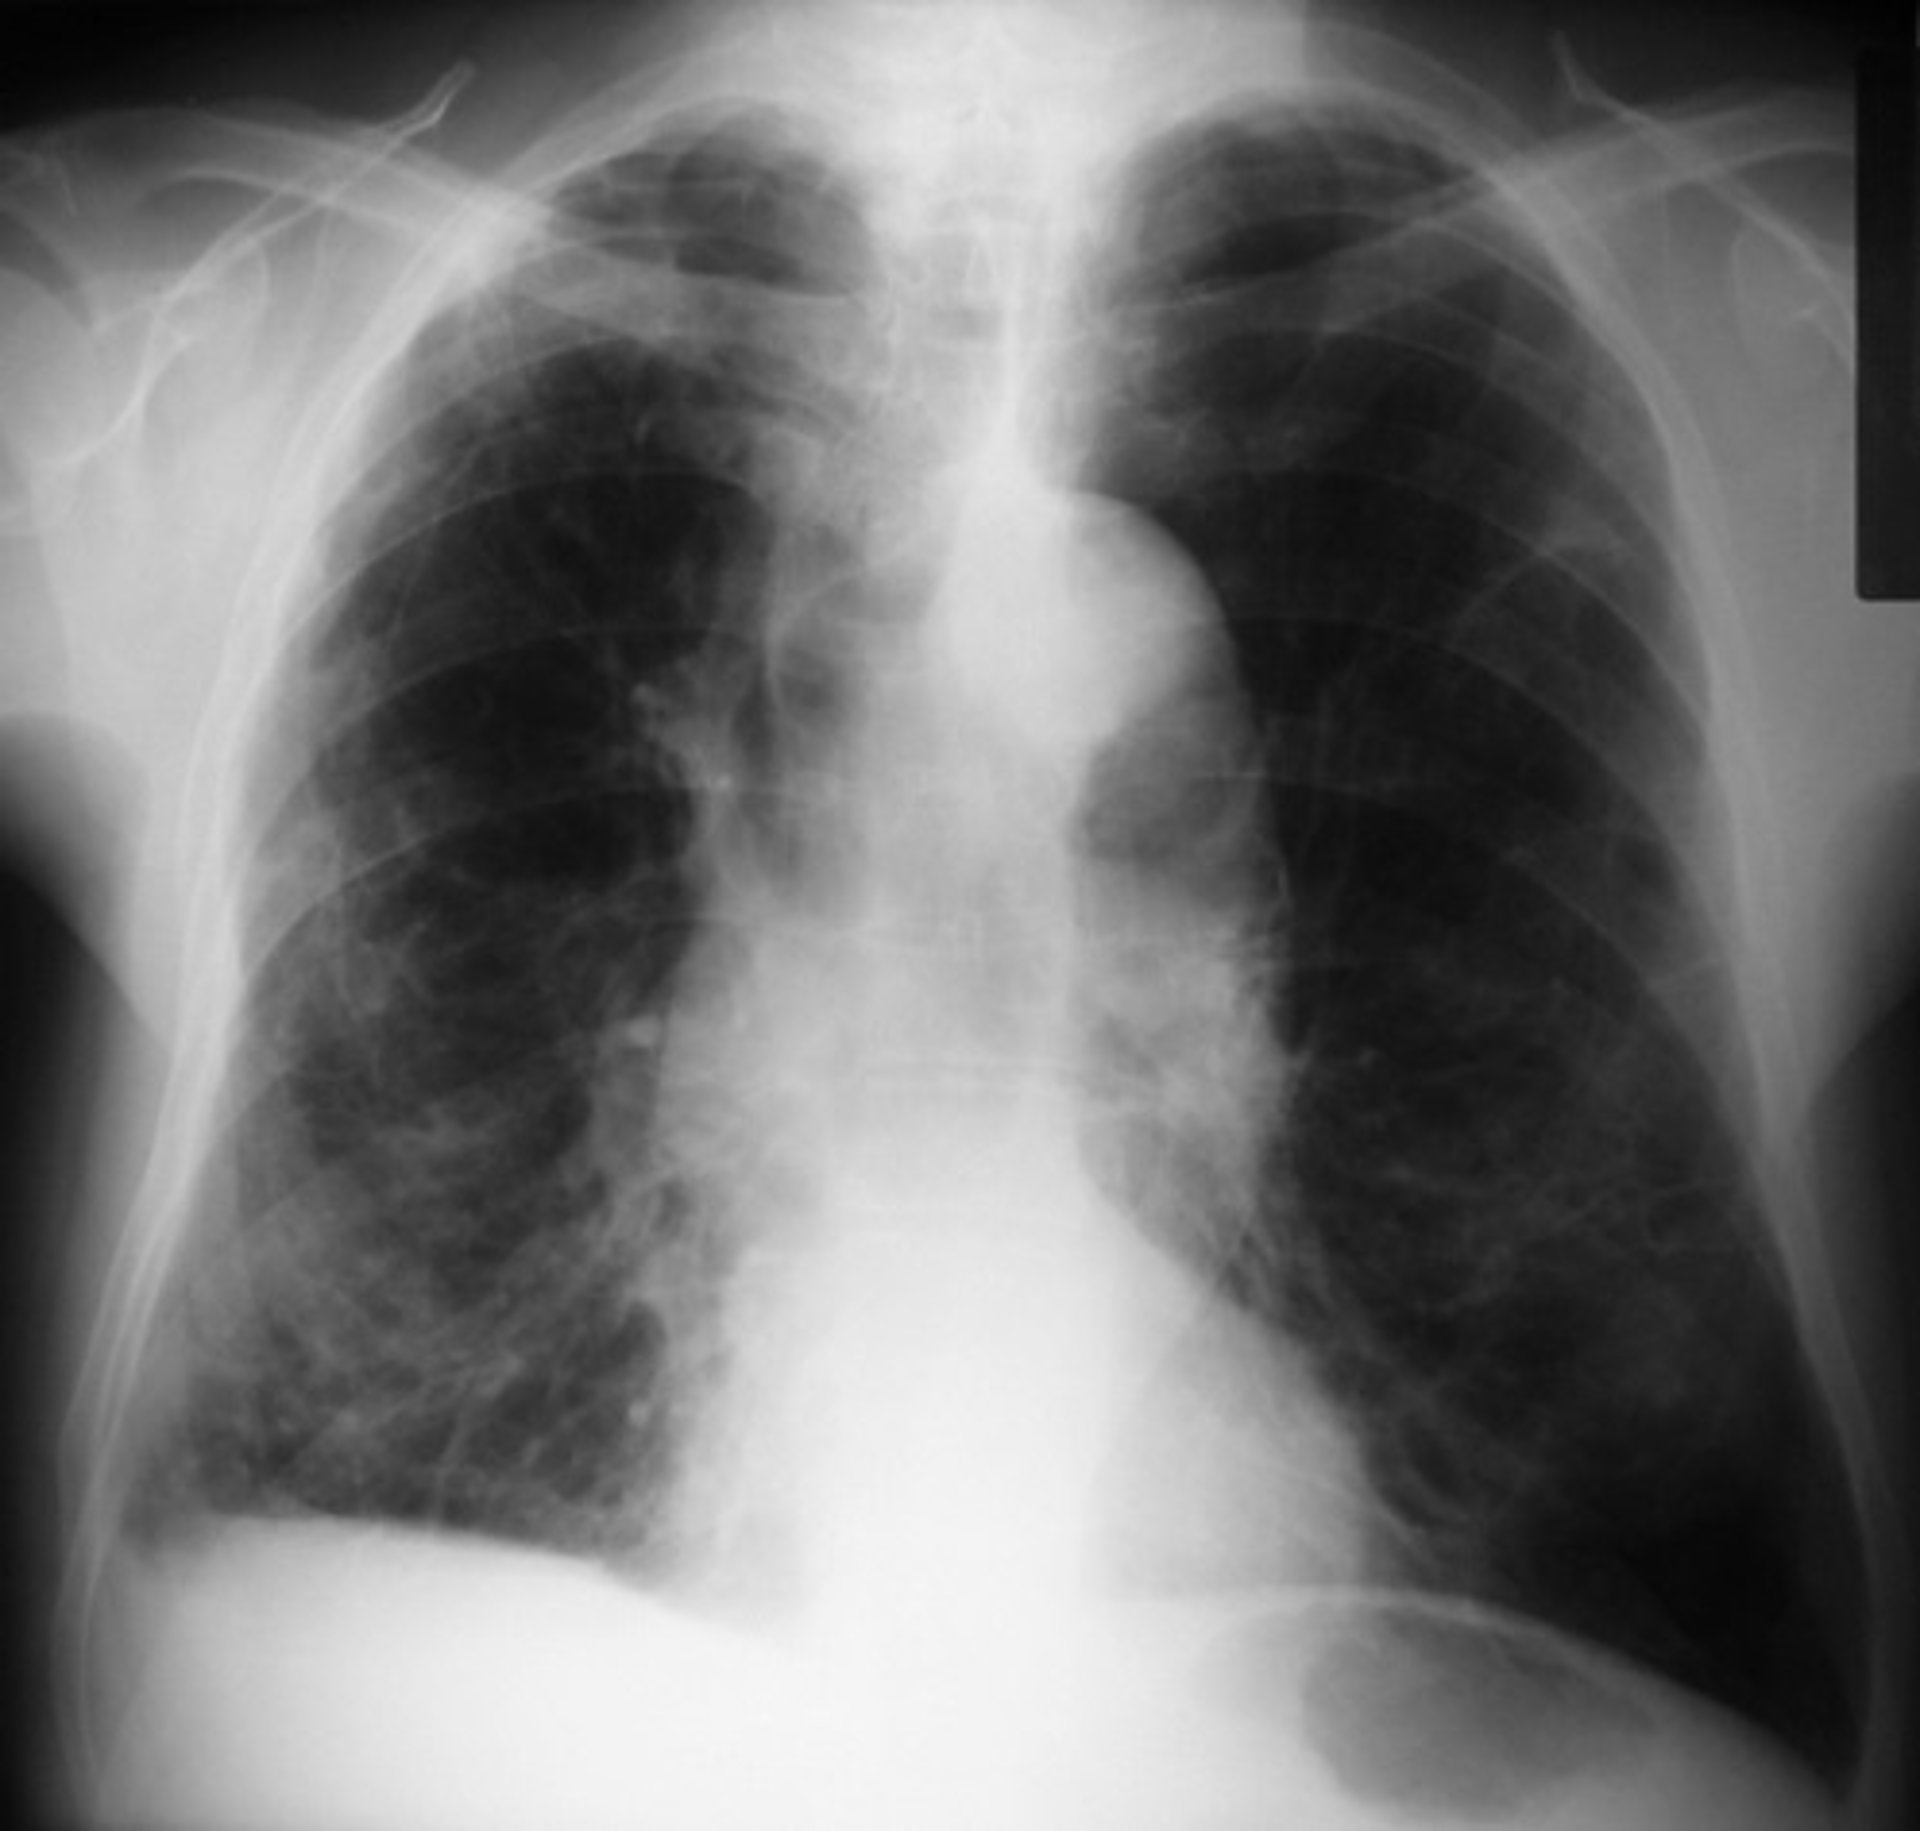

La EPOC es el nombre colectivo para las enfermedades pulmonares, incluyendo el enfisema, la bronquitis crónica y la enfermedad pulmonar obstructiva crónica. El tabaquismo es actualmente la principal causa de la EPOC y las posibilidades de desarrollar EPOC se elevan cuanto más tiempo esté fumando una persona.

Los pacientes que sufren EPOC presentan dificultades para respirar, debido principalmente a que el flujo de aire se obstruye, producen de manera persistente flema y tienen infecciones de pecho frecuentes. Con el tiempo, la inflamación conduce a cambios permanentes en los pulmones y las paredes de las vías respiratorias se espesan a medida que se produce más mucosidad.